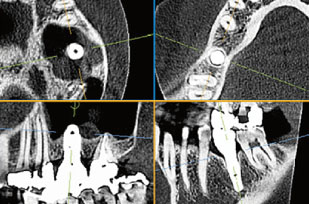

お口周りの状態・病変を立体画像で把握

従来のレントゲンでは平面画像のみで診断を行っておりました。しかし、堺市の歯医者 ゆうき歯科・矯正歯科クリニックが導入する歯科用3DCTでは口腔内の状態を立体画像で取得できます。

取得した画像から一般歯科はもちろんインプラント、矯正治療、親知らずの抜歯、歯周外科治療など幅広い症例において安全・的確な処置が可能です。

インプラントを埋入する場所の骨の厚み・硬さを診断して、適切なインプラント選択と処置をサポートします。